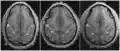

Transverse sections of brains of vervet monkey. It showing difference of the relative position of the left and right ascending ramus of the cingulate sulcus.